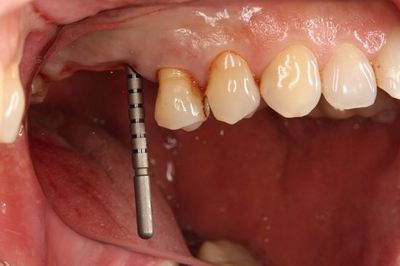

口腔内での適合を確認します。

スリーブの長さがありますので狭い口腔内でドリルを挿入するのは

熟練が必要です。